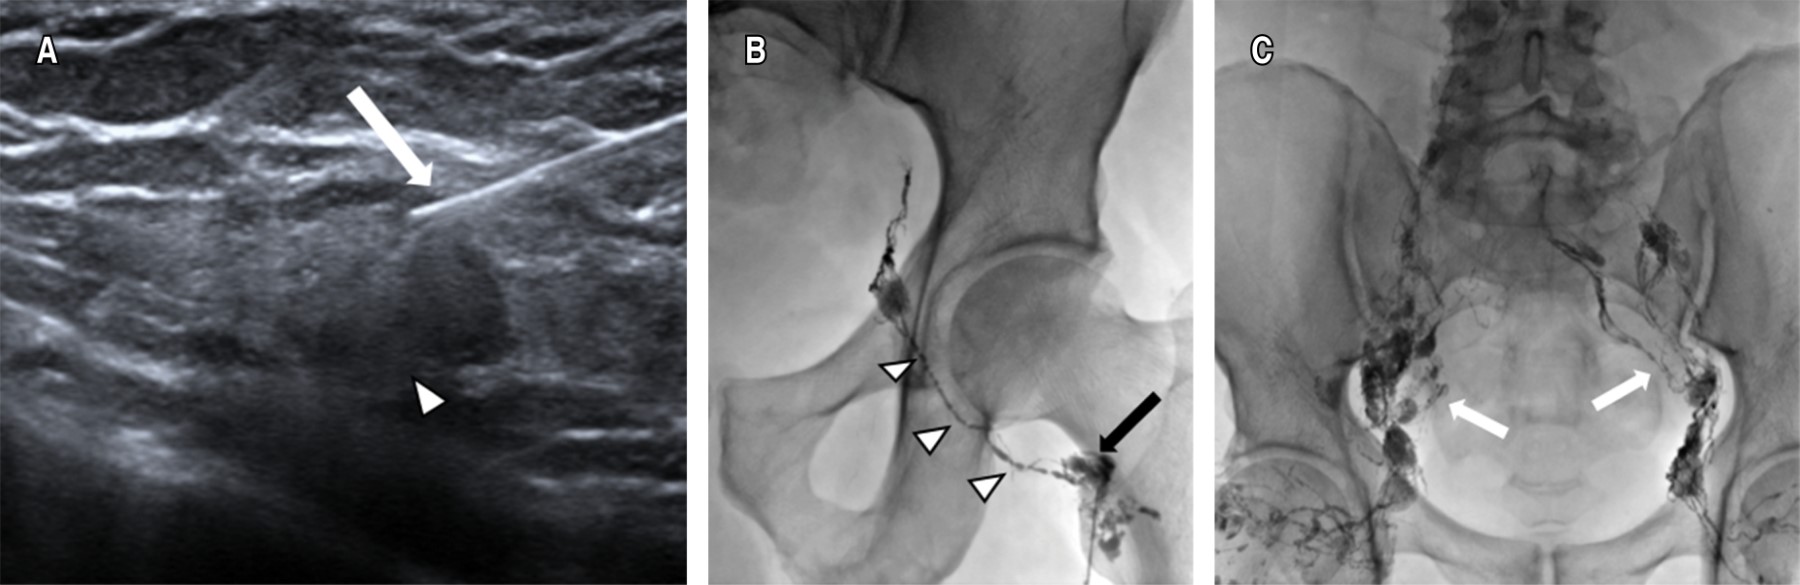

Linfangiografía intranodal (LG)

Se identificaron los ganglios inguinales bilaterales más grandes y distales a la región inguinal bajo guía ultrasonográfica; posteriormente se inyectó Lipiodol® utilizando una aguja de calibre 22 G, la punta de la aguja se coloca en la zona de transición entre la corteza y el hilio del ganglio linfático. Se realizó una inyección manual lenta del Lipiodol® y se observó bajo guía fluoroscópica a fin de confirmar la posición correcta de la aguja. Se inyecta un volumen total de 10 a 20 mL de Lipiodol®. Posteriormente se obtienen imágenes bajo control fluoroscópico cada cinco a 10 minutos durante el transcurso de la inyección de Lipiodol® para observar la progresión a través de los conductos linfáticos pélvicos y abdominales (Figura 1).

La linfangiografía intranodal se considera técnicamente satisfactoria si el ganglio linfático diana se selecciona con éxito y los canales linfáticos de interés, incluida la cisterna del quilo, se visualizan adecuadamente con Lipiodol®.